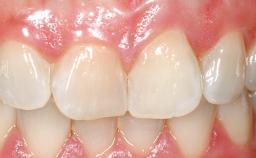

Late Placement of an Implant in a Maxillary Left Central Incisor Site

A 30-year-old female patient had lost tooth 21 and was referred to our clinic for consultation and treatment. Due to advanced apical infection, tooth 21 had been extracted two months earlier at another clinic and an acrylic-resin tooth had been bonded to the adjacent teeth. The patient desired implant treatment to avoid any damage to the adjacent natural teeth. While the patient had no history of any systemic disorder, she was a heavy smoker and exhibited medium to advanced periodontitis in the entire jaw. After the initial treatment to achieve a pocket probing depth of less than 4 mm and no bleeding on probing, a decrease in the height of the papillae mesial and distal to the extraction site and overall gingival recession were observed.

Prosthesis Type FDP